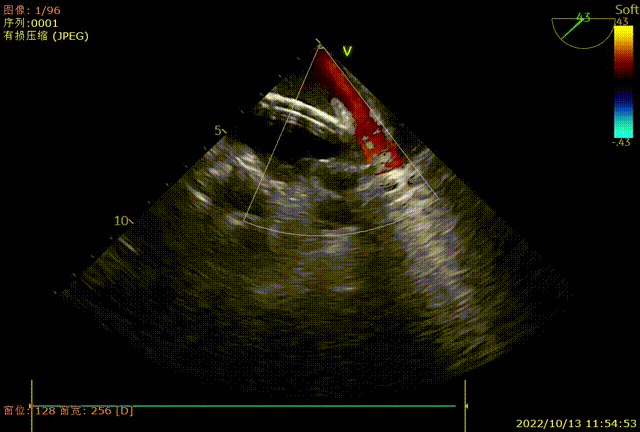

TAVR手术完成后,在TEE指导下,白明教授顺利偏下偏后完成了房间隔穿刺,同时TEE再次检查左心耳开口19-20mm。DSA造影观察与术前CTA多平面重建结果吻合,左心耳浅鸡翅型,测量左心耳开口24.9mm深度22mm。经过充分讨论和手术策略分析,决定为患者使用WATCHMAN FLX™ 31mm封堵器进行左心耳封堵。WATCHMAN FLX™器械由于和WATCHMAN设计的不同,导引鞘不需要进入左心耳远端,即可安全展开封堵器。术中白明教授送入WATCHAMN FLX™ 31mm输送系统后,退鞘形成FLX BALL,后采用进退结合法,“毛毛虫”式展开封堵器。造影观察封堵效果理想,牵拉试验稳定,在TEE上观察封堵器微露肩,压缩比21%,各角度无残余分流,最终释放左心耳封堵器。术后观察患者心包积液相比术前无变化,生命体征平稳,一站式手术顺利完成。

术中TEE各角度检查左心耳

TEE0度封堵效果

TEE45度封堵效果

TEE90度封堵效果

TEE135度封堵效果